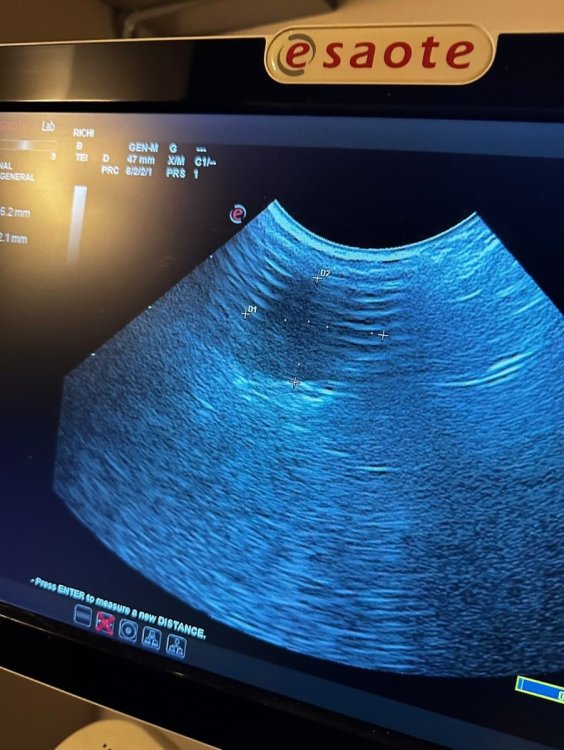

ДианаРикки Опубликовано 23 октября, 2024 #1 Опубликовано 23 октября, 2024 Вчера были на приеме у орнитолога, в Тбилиси. К сожалению, сказали очень печальный прогноз. Вес птицы всего лишь 28 грамм, критический. Сделали рентген, узи. Обнаружили кистообразную опухоль, начало подагры. Прикреплю вам файлы. И диагноз врача. Если вам не сложно, ознакомьтесь, пожалуйста. Сказали только обезбаливать анальгином. Больше никакого лечения. Даже предлагали усыпить, так как птица может испытывать боли, но рука не поднялась. Скажите, пожалуйста, насколько верен диагноз и настолько ли все плачевно или есть какие-то альтернативные варианты лечения? И можно что-то попробовать. Птица клюет шелушит зерна, но не ест. Пытаемся насильно кормить кашей. Отправили домой доживать свои дни. Не назначили никакого лечения, так как вес птицы очень мал. Также сказали не кормить насильно. Но я все де думаю, что опускать руки еще рано и может как-то можно набрать вес, чтобы провести лечение. Ведь подагру можно поддерживать , пока она не распространилась на органы. С каждым днем птице становится хуже. Прикрепляю диагноз врача и снимки рентгена. Спасибо